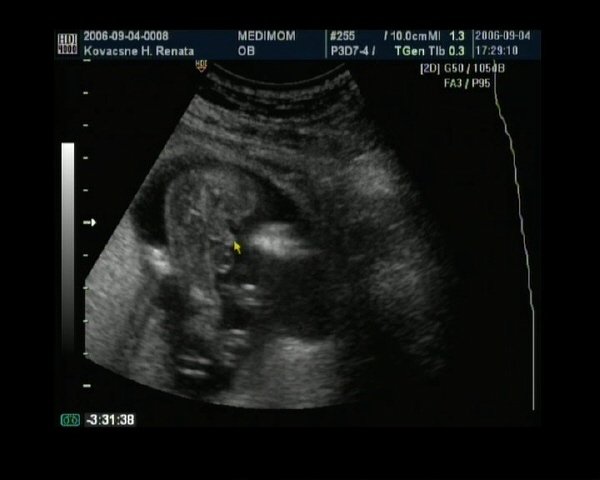

Kép Tuti bizonyték:ez itt kérem egy kuki!!

A sárga nyíl csúcsánál kezdődik a kuki, mögötte a kis zacsi.